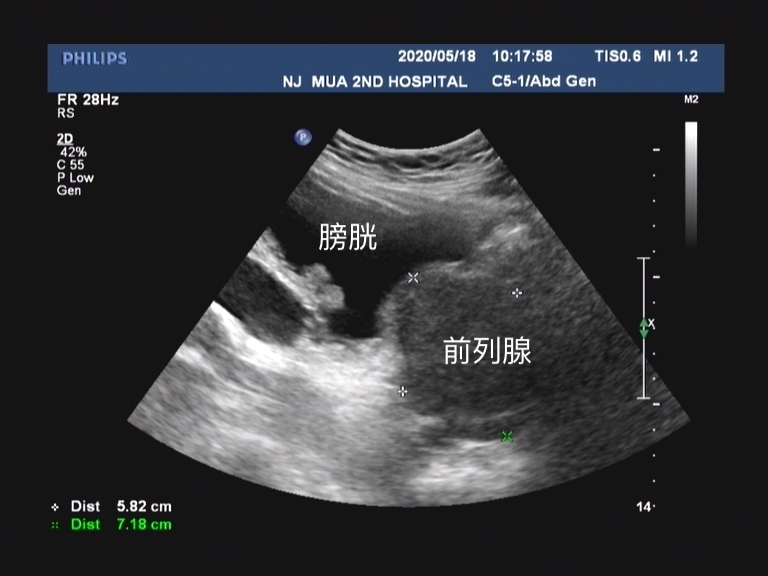

其实和临床我们确诊前列腺增生这个病有一些区别的地方在于 ,彩超给予患者前列腺增生这个诊断时候,是通过测量患者的前列腺体积。 超声检查可以了解 前列腺的形态、体积、有无异常回声、凸入膀胱的程度和残余尿量 。 前列腺体积的测量公式为0.52*前后径*左右径*上下径。

超声的诊断标准中, 如果测量的前列腺体积超过4cm*3cm*2cm时 ,在报告中就会描述为前列腺增生。因为患者的前列腺体积的确增大了。 而前列腺增生最主要的病理生理改变就是由于体积增大导致后尿道延长、受压变形、狭窄和尿道阻力增加。 这种前列腺体积增大就意味着从超声的角度可以诊断患者为前列腺增生。